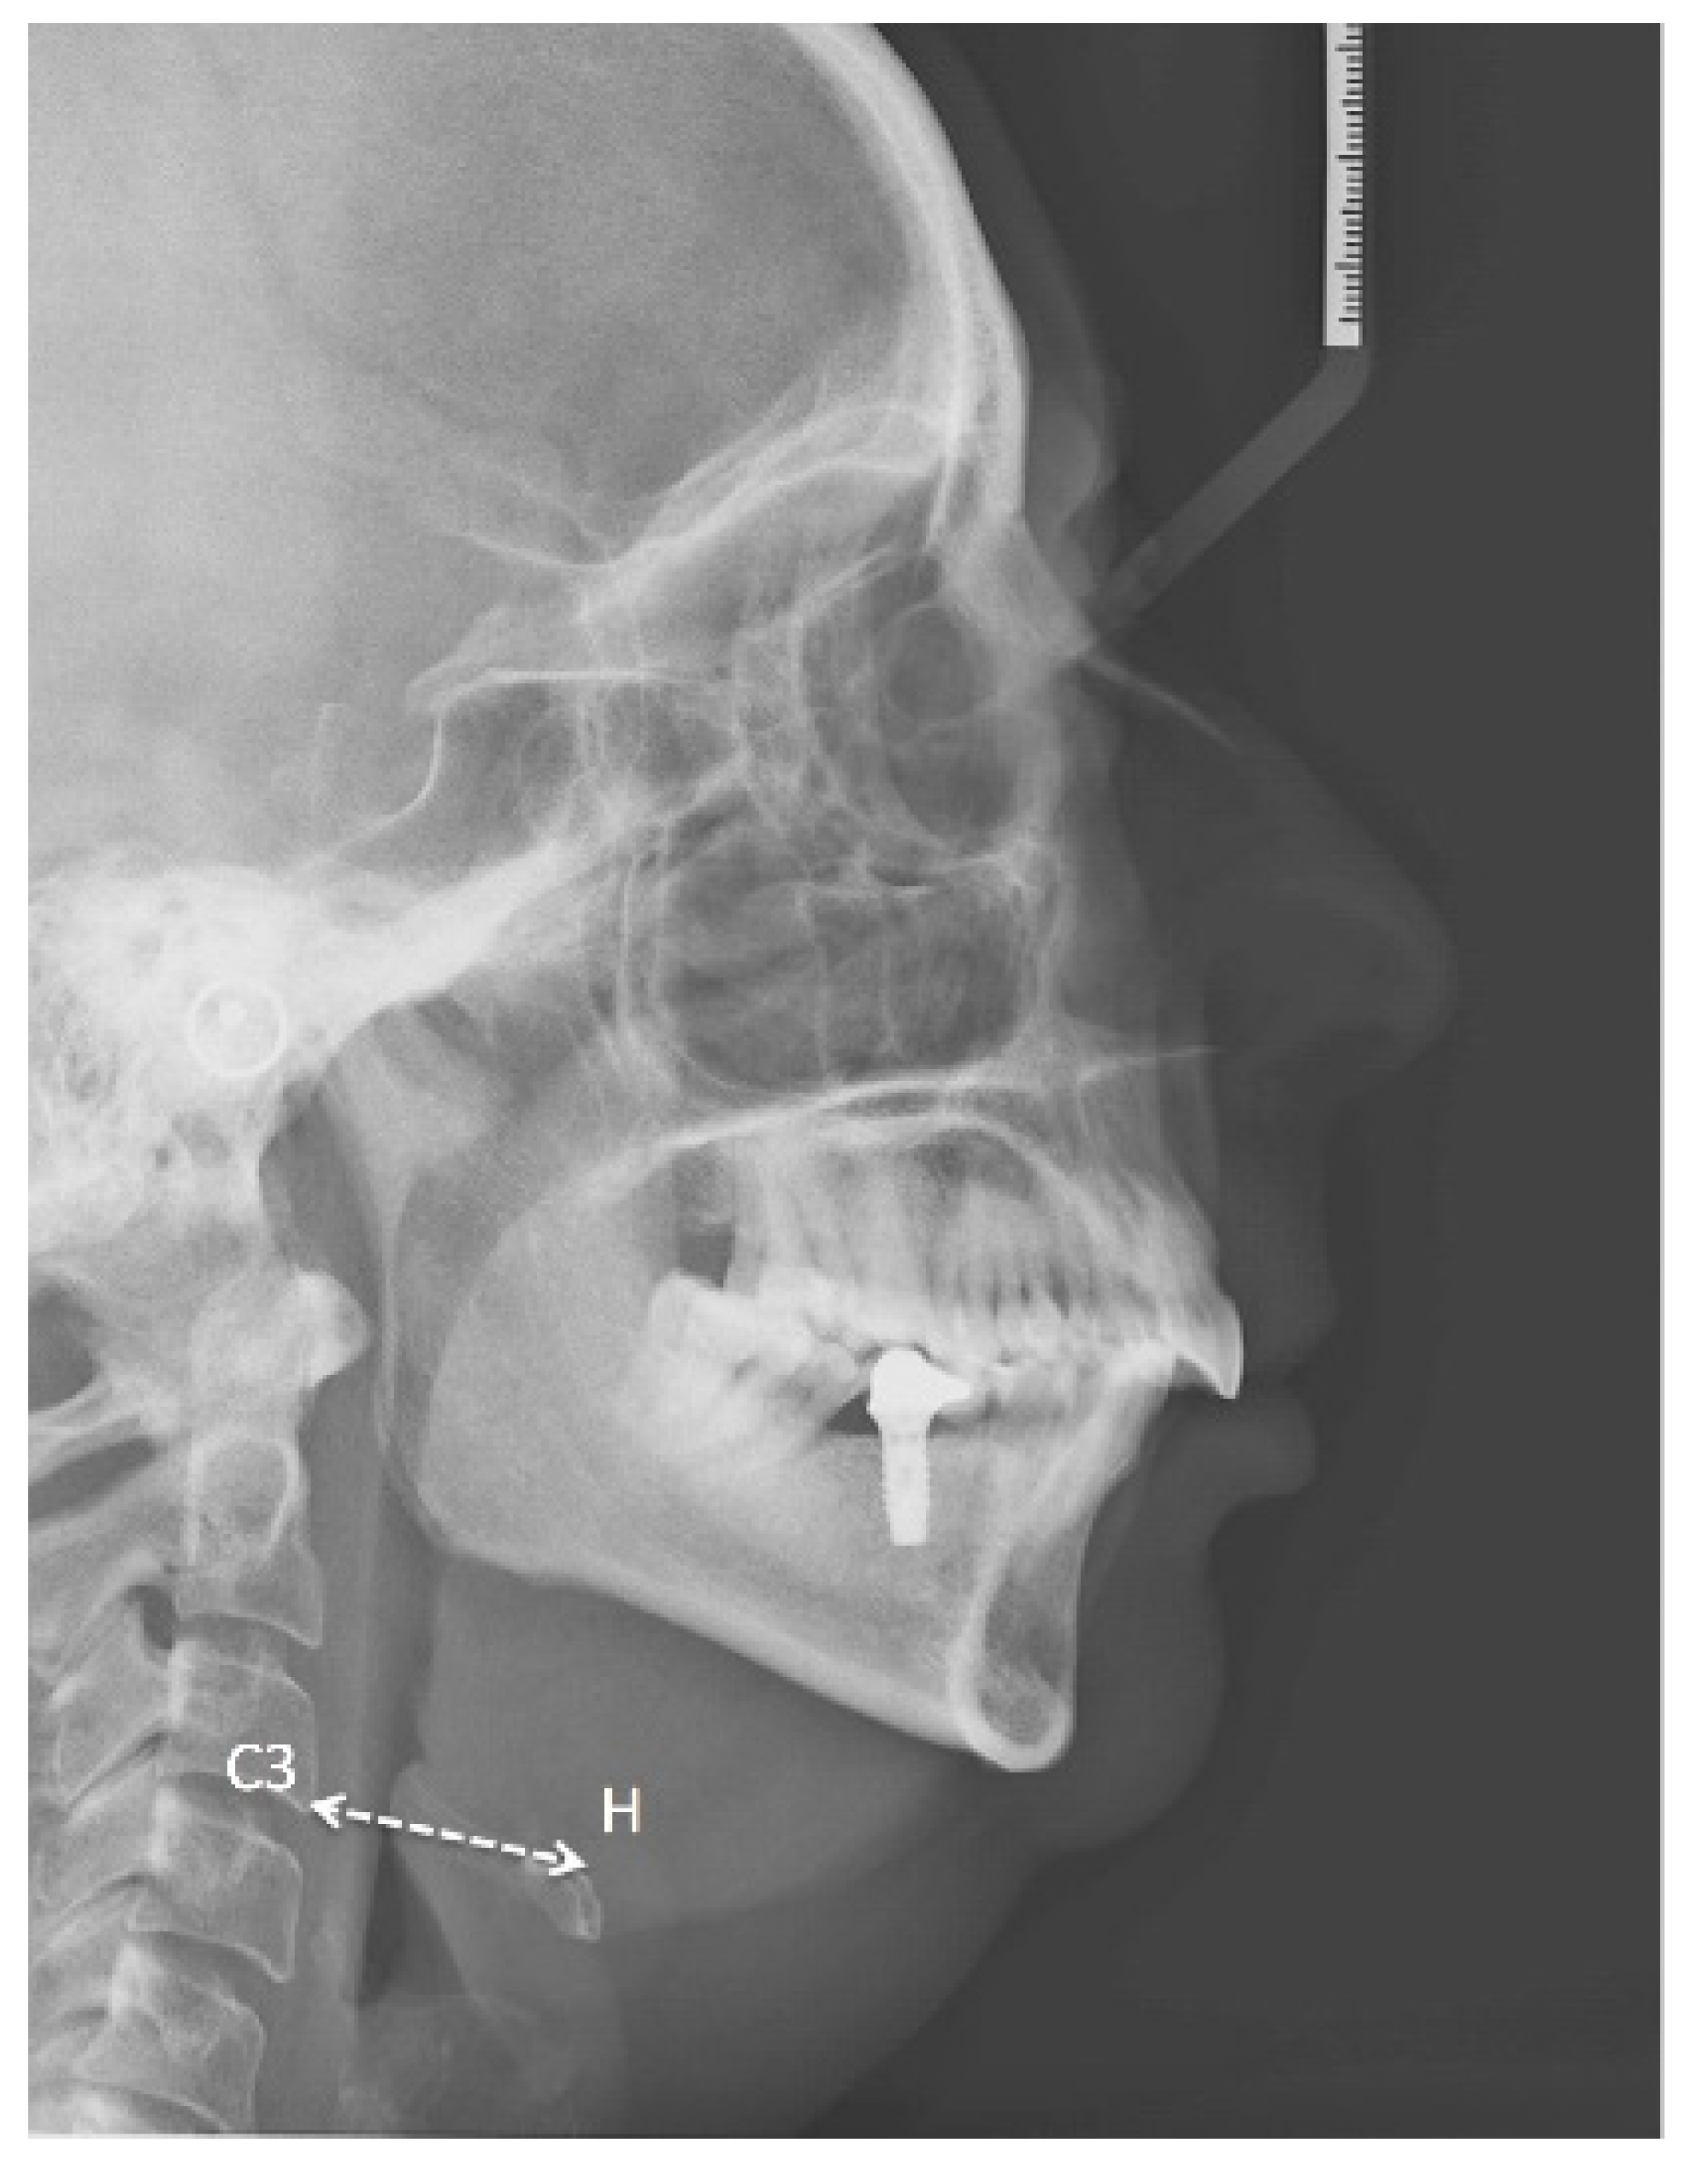

| 13. C3H | H-C3 Line joining point H with point C3. |

| 16. PNSP | PNS to P (see Figure 1). Length of the soft palate. |

| 18. SPAS | Superior airway space. Measurement (mm) of the airway between the soft palate and the posterior pharyngeal wall along a line parallel to the Go-B plane, passing through the most posterior and superior point of the soft palate. |

| 19. MAS | Middle airway space. Measurement (mm) of the airway between the anterior wall and the posterior pharyngeal wall along a line parallel to the Go-B plane, passing through point P. |

| 20. IAS | Inferior airway space. Measurement (mm) of the airway located between the anterior wall and the posterior pharyngeal wall along the Go-B line. |

| 21. VAL | (PNS-Eb) Oropharyngeal length. |